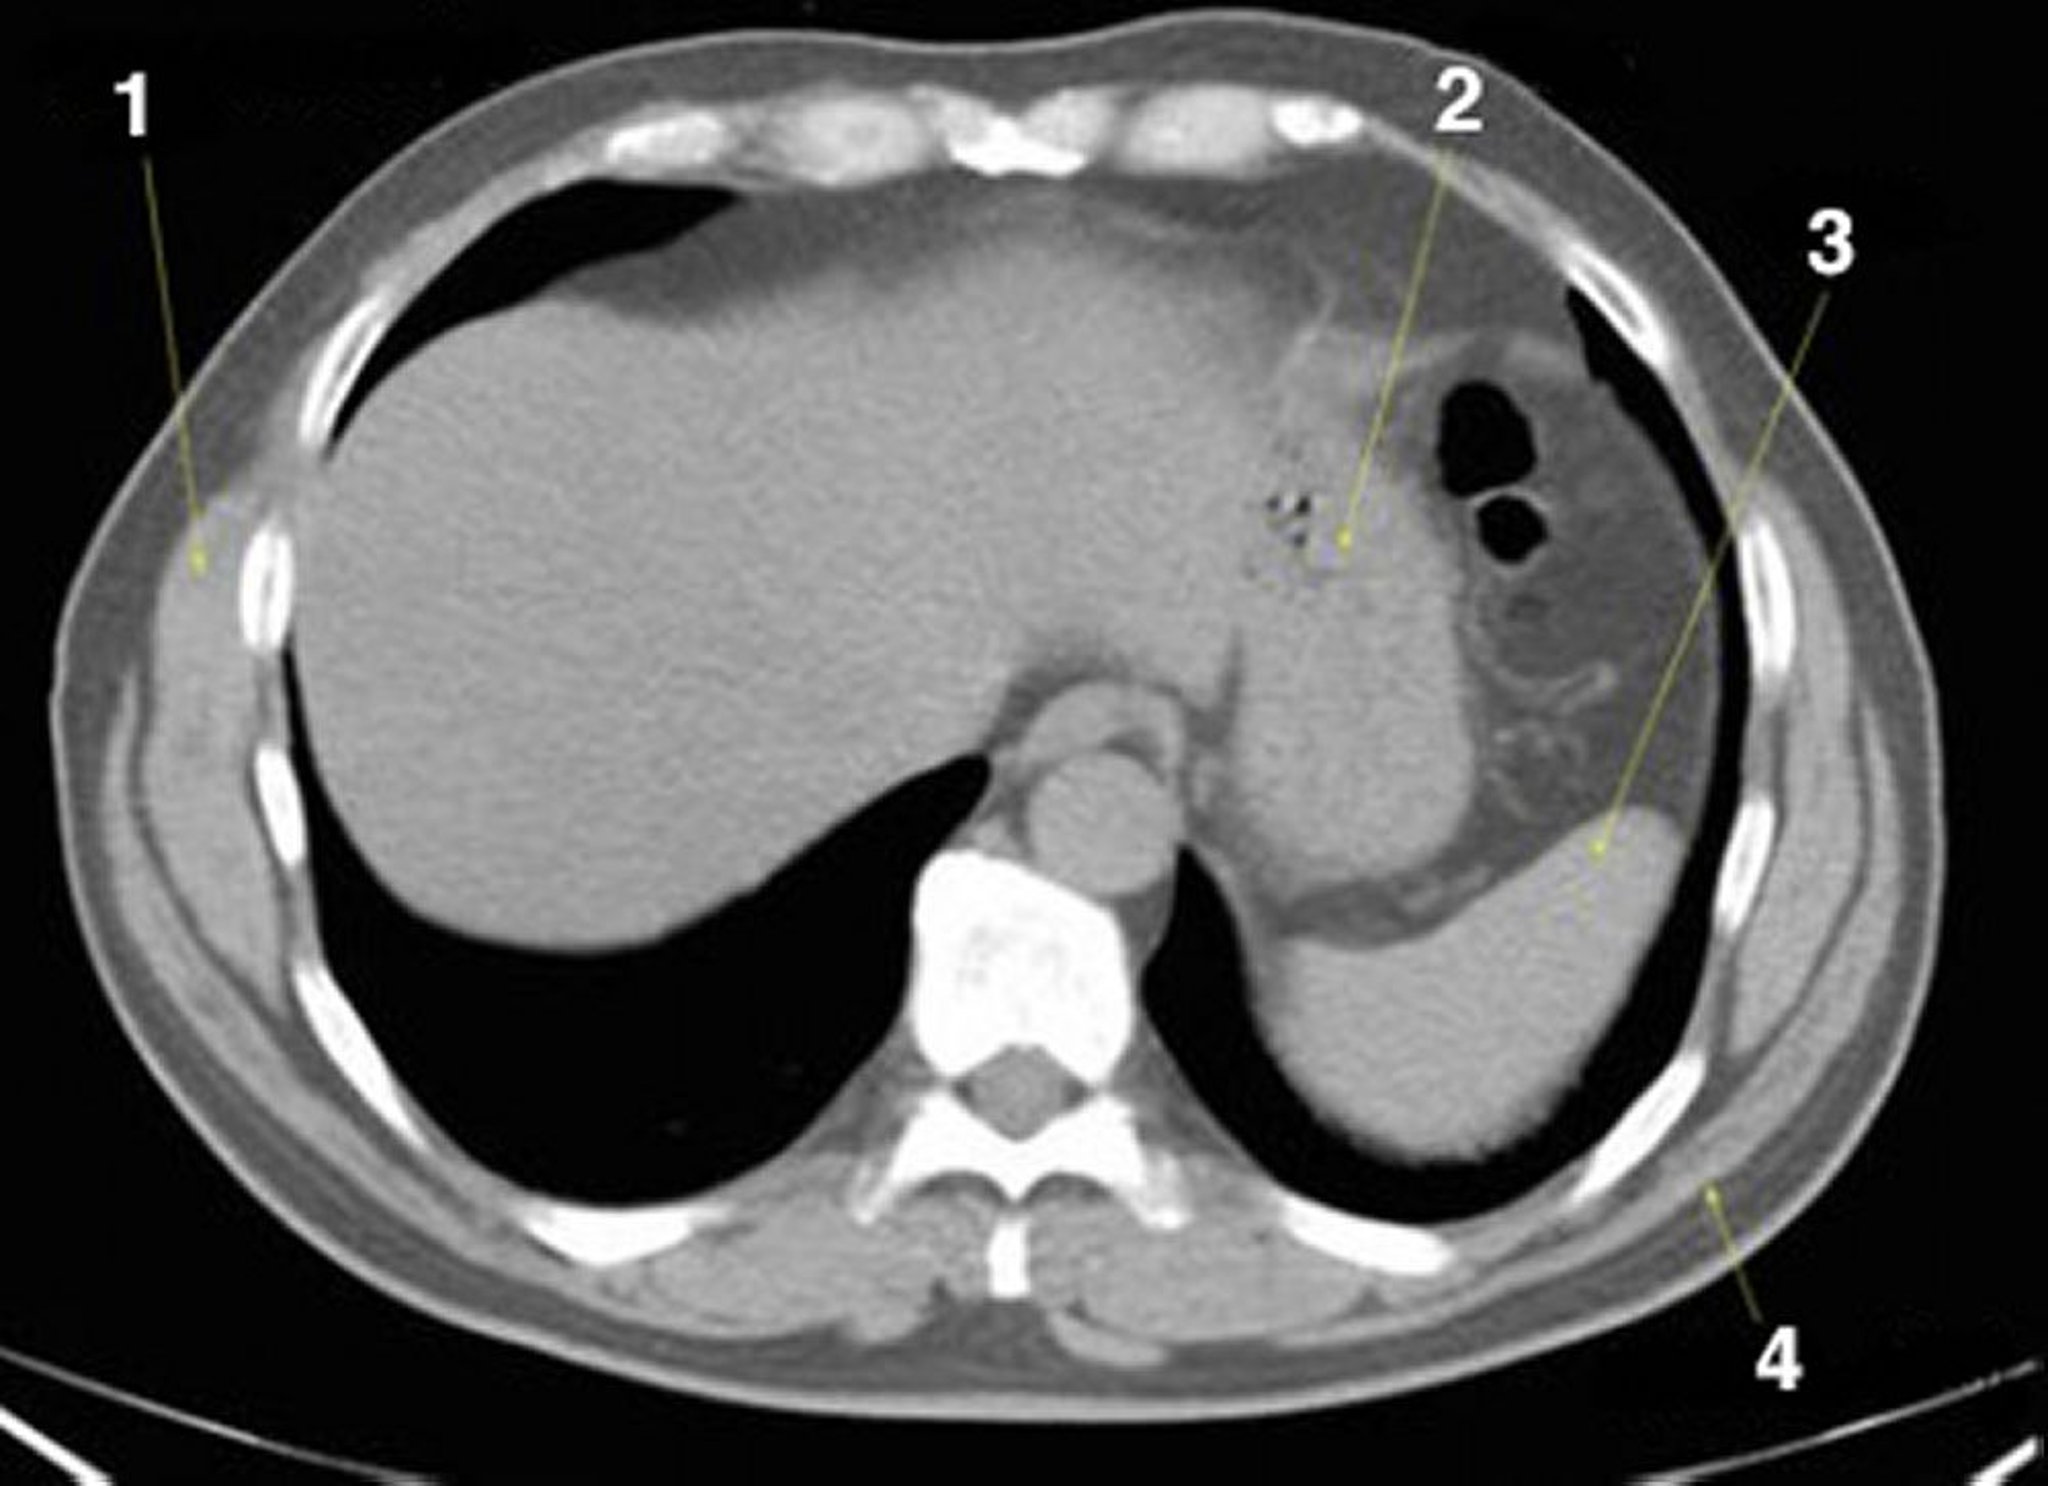

TC sem contraste do abdome e da pelve mostrando anatomia normal (lâmina 2)

1 = serrátil anterior; 2 = estômago; 3 = baço; 4 = latíssimo do dorso.